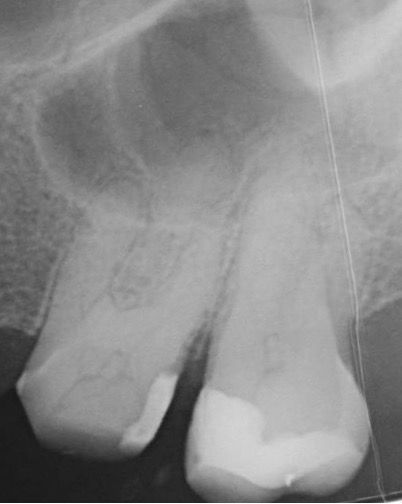

45 yaşında sağlıklı kadın hasta, 2023 Mayıs ayında protetik gereksinimden dolayı prepare edilen 26 numaralı dişinde işlem sonrası gelişen şiddetli ağrı şikayeti ile kliniğimize başvurdu İlgili dişe kök kanal tedavisi işlemi planlandı (Şekil 1).

(Şekil 1) 2023 Mayıs 26 No Pre-Op radyografi.